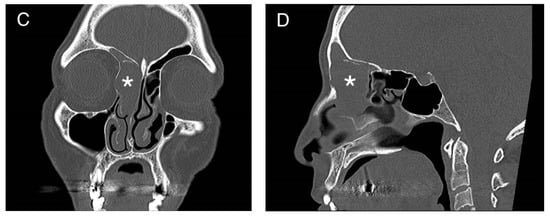

Figure 2.

Visualization of the embolized mass in white (3D view). R = right.